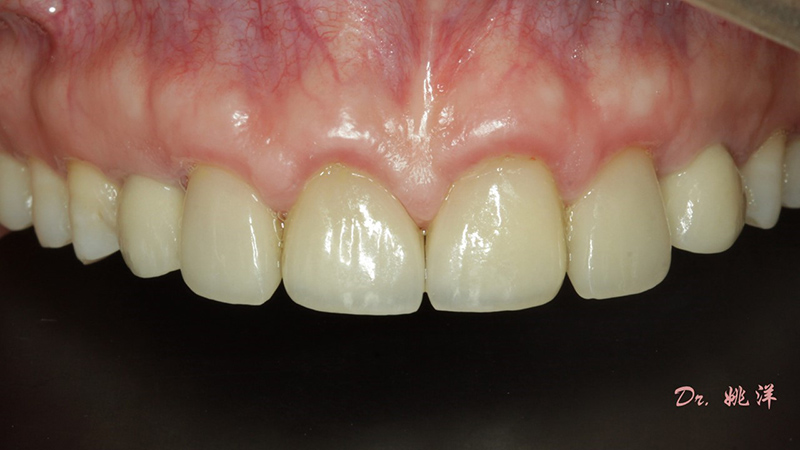

種植后數(shù)字化取模,前牙美學(xué)間隙精確分配

從最終修復(fù)效果可以看出:23,24間隙不足修復(fù)兩顆,修復(fù)為1顆牙。因?yàn)榻?jīng)過(guò)數(shù)字化設(shè)計(jì)和精確導(dǎo)航植入,修復(fù)體齦緣協(xié)調(diào)自然

術(shù)后照片

恢復(fù)了正常的淺覆合淺覆蓋